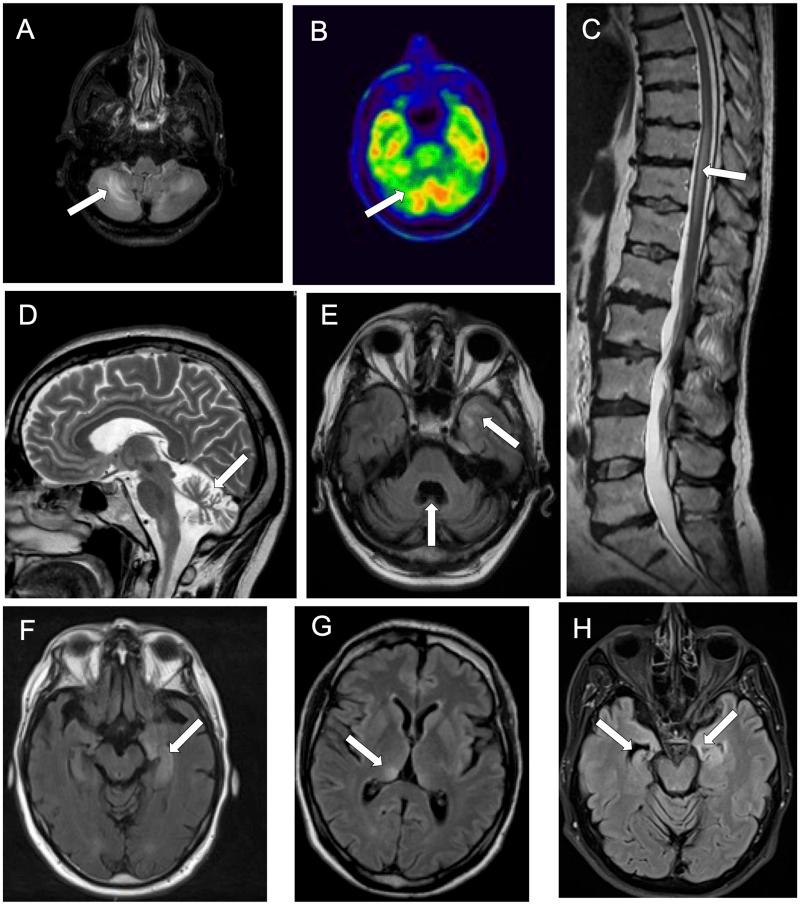

In this study, we report the clinical features of Kelch-like protein 11 antibody-associated paraneoplastic neurological syndrome, design and validate a clinical score to facilitate the identification of patients that should be tested for Kelch-like protein 11 antibodies, and examine in detail the nature of the immune response in both the brain and the tumour samples for a better characterization of the immunopathogenesis of this condition. The presence of Kelch-like protein 11 antibodies was retrospectively assessed in patients referred to the French Reference Center for paraneoplastic neurological syndrome and autoimmune encephalitis with (i) antibody-negative paraneoplastic neurological syndrome [limbic encephalitis ( = 105), cerebellar degeneration ( = 33)] and (ii) antibody-positive paraneoplastic neurological syndrome [Ma2-Ab encephalitis ( = 34), antibodies targeting N-methyl-D-aspartate receptor encephalitis with teratoma ( = 49)]. Additionally, since 1 January 2020, patients were prospectively screened for Kelch-like protein 11 antibodies as new usual clinical practice. Overall, Kelch-like protein 11 antibodies were detected in 11 patients [11/11, 100% were male; their median (range) age was 44 (35-79) years], 9 of them from the antibody-negative paraneoplastic neurological syndrome cohort, 1 from the antibody-positive (Ma2-Ab) cohort and 1 additional prospectively detected patient. All patients manifested a cerebellar syndrome, either isolated (4/11, 36%) or part of a multi-system neurological disorder (7/11, 64%). Additional core syndromes were limbic encephalitis (5/11, 45%) and myelitis (2/11, 18%). Severe weight loss (7/11, 64%) and hearing loss/tinnitus (5/11, 45%) were common. Rarer neurologic manifestations included hypersomnia and seizures (2/11, 18%). Two patients presented phenotypes resembling primary neurodegenerative disorders (progressive supranuclear palsy and flail arm syndrome, respectively). An associated cancer was found in 9/11 (82%) patients; it was most commonly (7/9, 78%) a spontaneously regressed ('burned-out') testicular germ cell tumour. A newly designed clinical score (MATCH score: male, ataxia, testicular cancer, hearing alterations) with a cut-off ≥4 successfully identified patients with Kelch-like protein 11 antibodies (sensitivity 78%, specificity 99%). Pathological findings (three testicular tumours, three lymph node metastases of testicular tumours, one brain biopsy) showed the presence of a T-cell inflammation with resulting anti-tumour immunity in the testis and one chronic, exhausted immune response-demonstrated by immune checkpoint expression-in the metastases and the brain. In conclusion, these findings suggest that Kelch-like protein 11 antibody paraneoplastic neurological syndrome is a homogeneous clinical syndrome and its detection can be facilitated using the MATCH score. The pathogenesis is probably T-cell mediated, but the stages of inflammation are different in the testis, metastases and the brain.